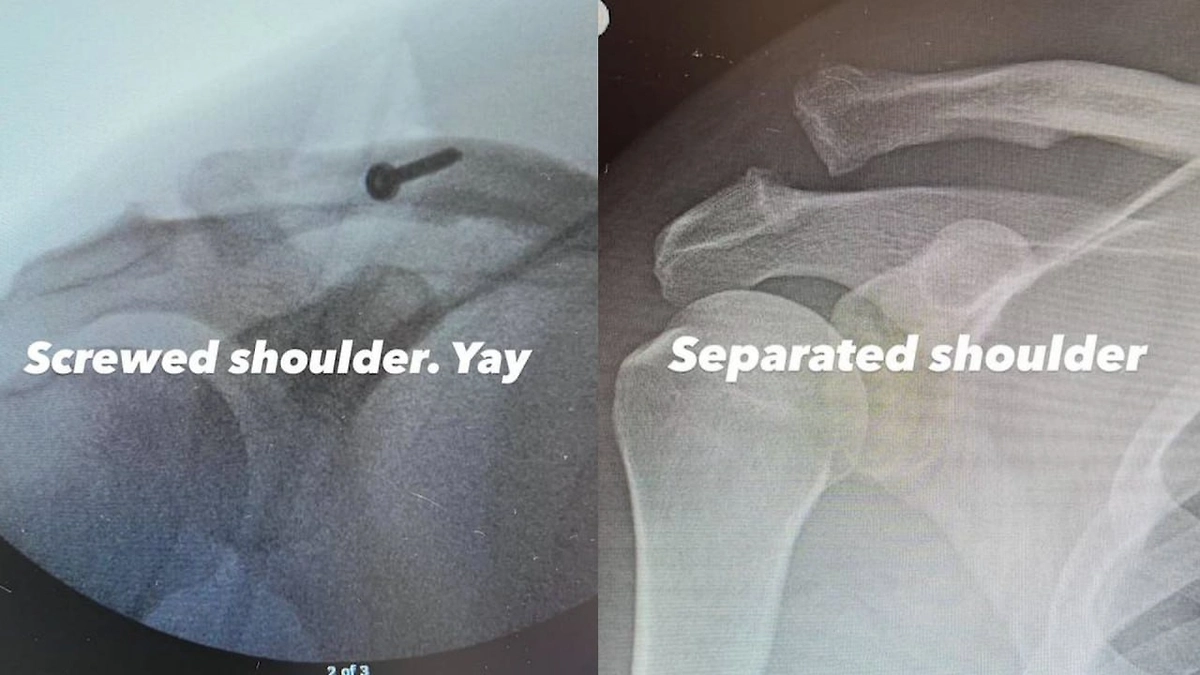

Ченнинг Татум загремел на больничную койку с серьёзной травмой — отрывом акромиона. Она возникает при разрыве и растяжении связок в месте соединения ключицы с лопаткой.

Звезда целого множества голливудских фильмов, в том числе последнего «Дэдпула» и «Мачо и Ботан» не рассказал, как именно травмировался. Судя по рентгеновским снимкам, врачи вставили в его плечо некую металлическую конструкцию, похожую на болт.

Травмы Ченнинга Татума. Коллаж © Instagram (признан экстремистской организацией и запрещён на территории Российской Федерации) / channingtatum